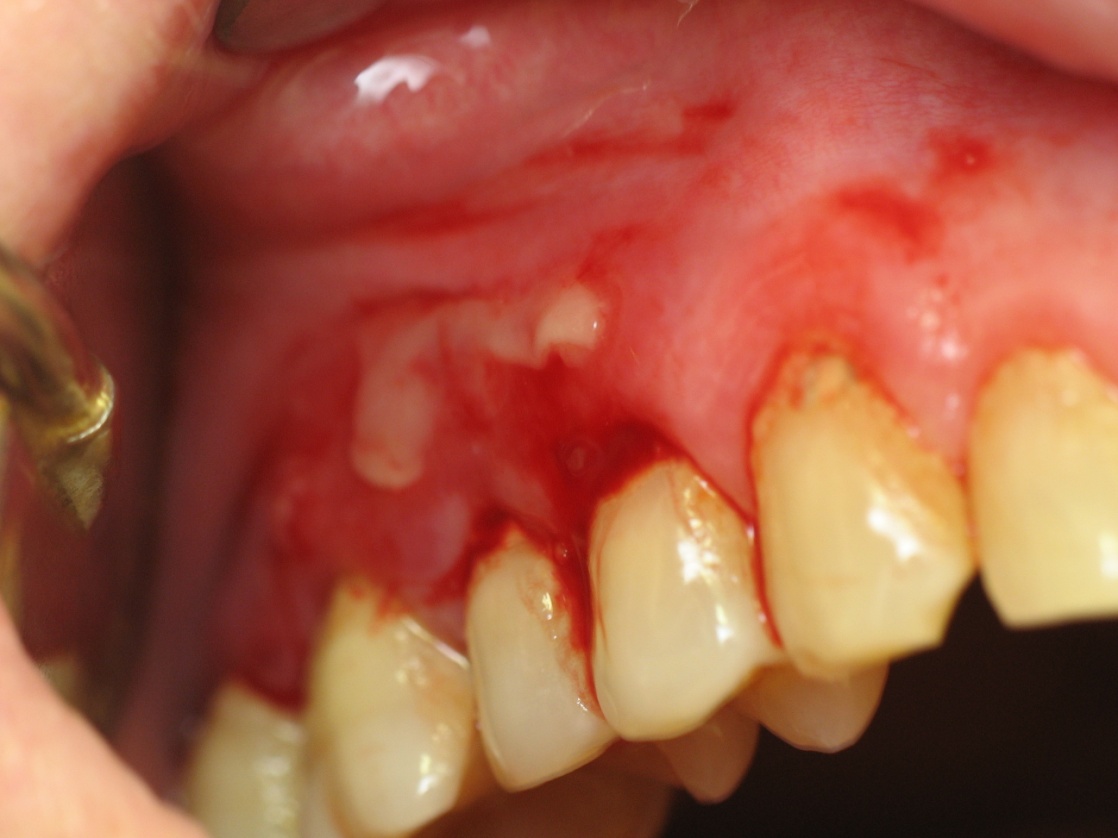

Типичные симптомы ДГ выявляли у пациентов с диагнозом вульгарной пузырчатки (ВП; L10), подтвержденным клинически и цитологически по факту обнаружения акантолитических клеток Тцанка в мазках-отпечатках с элементов поражения. На долю этих клинических вариантов МПП в общей структуре гингивита приходилось 23,2 % (13 пациентов). Жалобы со стороны полости рта у этих пациентов сводились к сильной боли, жжению и покраснению десен, повышенному слюноотделению, затрудненному приему пищи и проблемам ГПР. Объективно на десне, преимущественно в области переднего и боковых (правого/левого) зубочелюстных сегментов, выявляли множественные эрозии линейной или полигональной формы, легко кровоточащие, чаще покрытые некротическим налетом (рис. 3). Эрозированные участки десны обнаруживали на всех топографических зонах десны: маргинальной, папиллярной, прикрепленной и т.д. В 76,9 % случаев эрозивный процесс был генерализованным, распространялся на области 3–4 десневых секстантов. У всех пациентов был выявлен положительный симптом Никольского. У одного из больных отмечены пузырные элементы на коже спины, он состоял на учете в КОД по поводу ВП. C учетом классификации ДГ по Glickman, у больных вульгарной пузырчаткой практически в равной мере выявляли случаи средне- и тяжелого десквамативного процесса (6; 46,2 % и 7; 53,8 % соответственно).

Рис. 3. Больной С., 42 года. Диагноз: изолированное поражение десны в форме десквамативного гингивита (разлитая эритема, эрозии, геморрагические пузыри на слизистой вестибулярной поверхности десны верхне-бокового/правого сегмента) при вульгарной пузырчатке